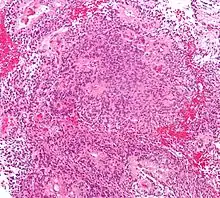

Micrograph of an ependymoma. H&E stain. | |

Ependymomas are composed of cells with regular, round to oval nuclei. There is a variably dense fibrillary background. Tumor cells may form gland-like round or elongated structures that resemble the embryologic ependymal canal, with long, delicate processes extending into the lumen; more frequently present are perivascular pseudorosettes in which tumor cells are arranged around vessels with an intervening zone consisting of thin ependymal processes directed toward the wall of the vessel.[4]